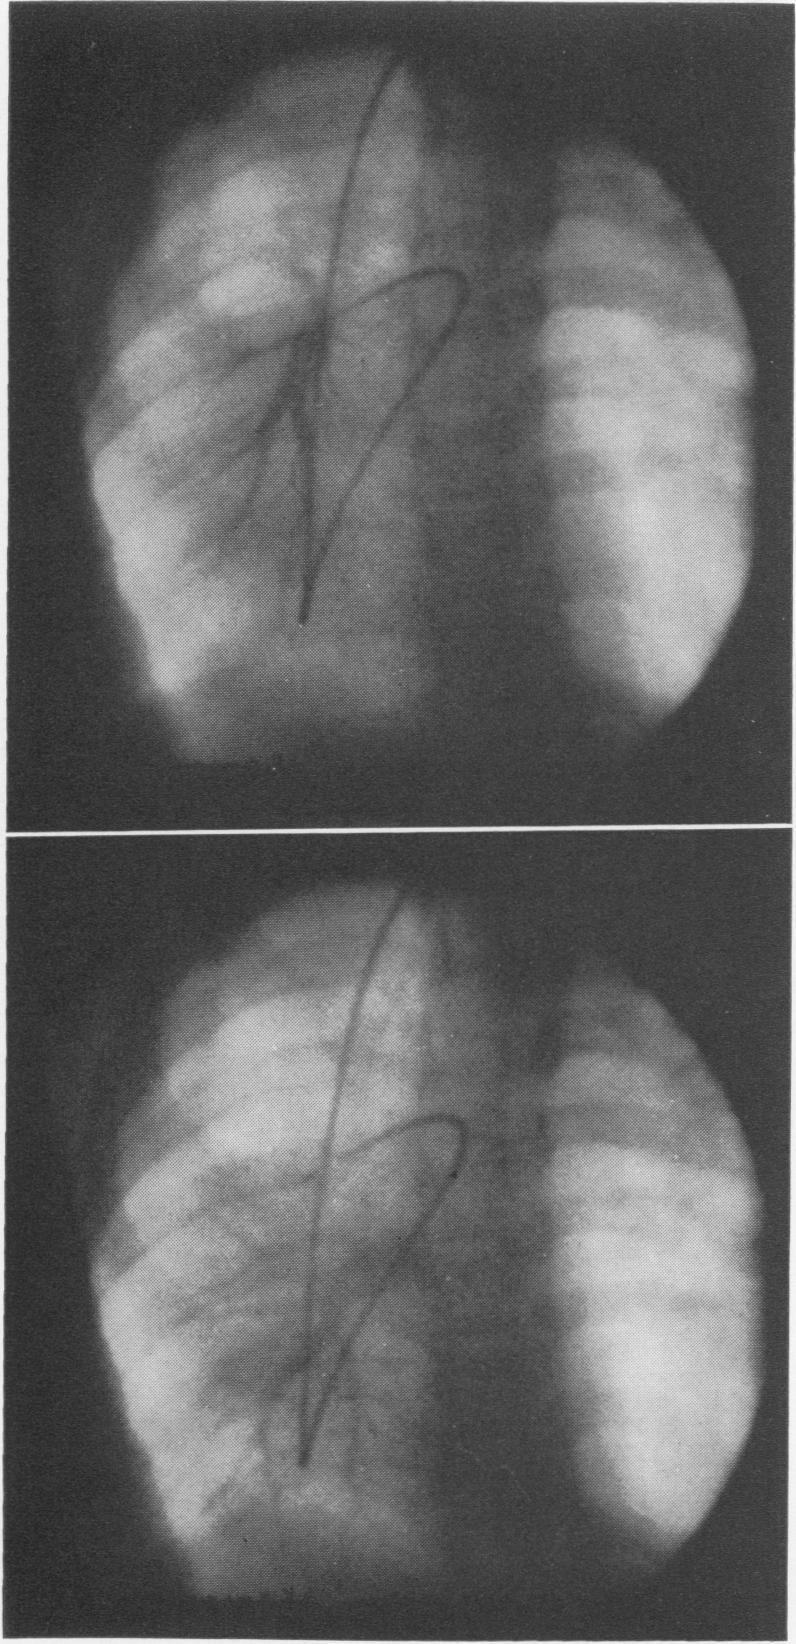

Traumatic rupture of the right main bronchus in an eight-year-old child successfully repaired eight years after injury.

Ann Surg. 1970 Dec;172(6):1039-47. doi: 10.1097/00000658-197012000-00018.